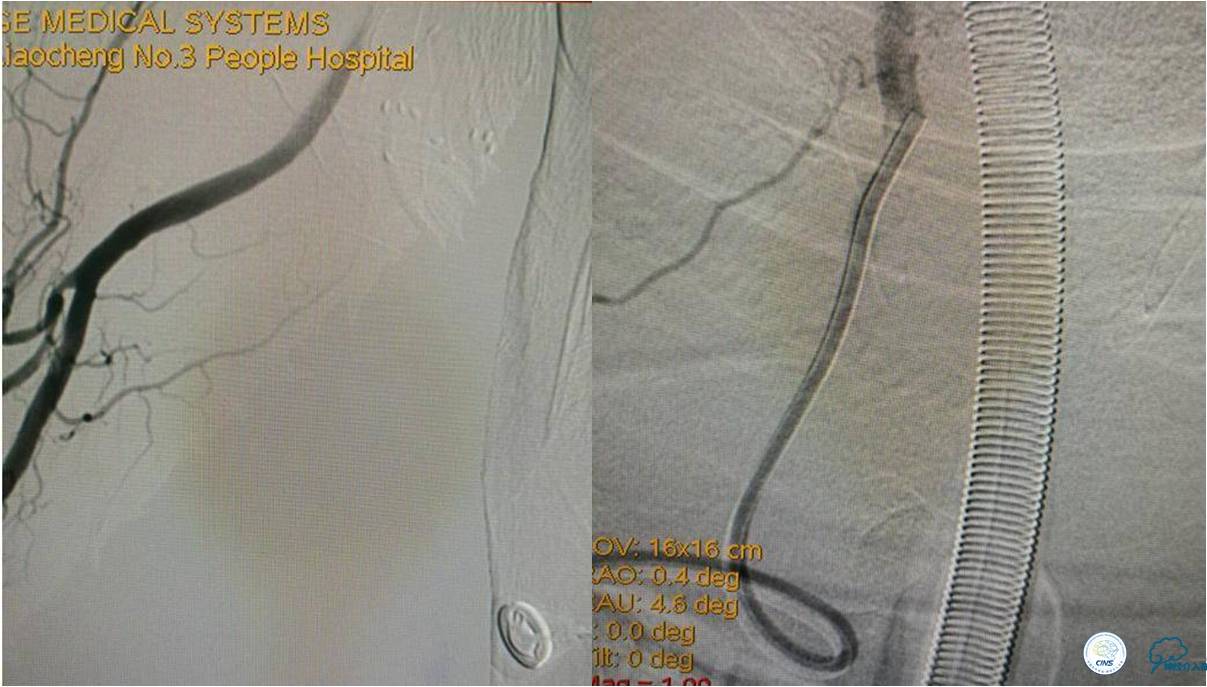

》DSA资料(经桡动脉,5F导引导管)

》DSA资料(第3次取栓)

第3次取出血栓